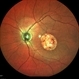

- hereditary retinal degeneration, hereditary retinal dystrophy, rod cone dystrophy

- Fundus autofluorescence of the left eye in a 58 yo male with rod cone dystrophy. He presented with night blindness and peripheral vision loss since youth and recent decrease in central vision for the past 10 years. Notice multiple coin shaped hypoautofluorescent pacthes within central 20 degrees which are coalescing centrally. (fundus photo uploaded separately) He has one pathogenic variants of both CEP290 and PRPH2 genes.